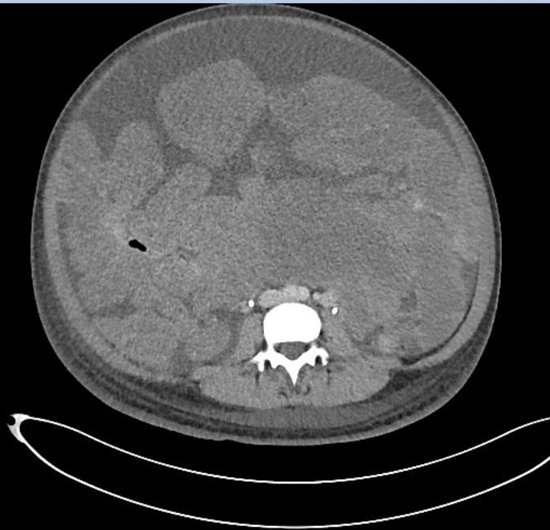

他把那里比作“布满鹅卵石的海滩”。原本应该是肠管的位置看不到一段肠子,只有挤作一团的肿瘤。腹腔内唯一可见的正常器官是胃的下部。血管被挤到一旁,由于供养着密密麻麻、黄豆到蚕豆大小的肿瘤,直径变成正常血管的3倍。

“无从下刀”,他用手摸,肿瘤的质地较软、呈粉红色,看上去、摸起来都与肠管无异。卵巢和子宫隐藏在盆腔深处。

肿瘤太多,一个一个切太慢,谭先杰决定使用“卷地毯式”,彻底清除肠管和膀胱表面成串的肿瘤,“就是从它们的表面扒掉一层,还不能扒太多。”

他先用镊子将白色蚯蚓般的输尿管从腹膜上分离,推到一旁。接着确认两大血管——髂外动脉和静脉的位置,确保它们不被损伤。

接着他用手术刀将将布满肿瘤的腹膜从其下的器官表面剥离出来,用手脱出,“兜满瘤子,像口袋一样”。

3小时后,“地毯”卷走,子宫和双侧卵巢终于显露出来,“柳暗花明又一村”。

切下的瘤子快要从4个口径22厘米、容积1000毫升的手术大盆和1个手术弯盘中溢出来。谭先杰把它们铺满100厘米×100厘米的手术大单上,花了10多分钟计数。

肿瘤一共1150多枚,手术中瘤体内带走的血液足有2600毫升,约5斤重。其中最大的瘤子尺寸18厘米×15厘米×8厘米,最小的只有黄豆大小。去掉几大块被送去病理检查的肿瘤,余下肿瘤重18斤。